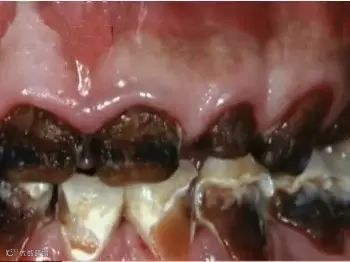

2.增加患龋齿的风险——牙牙不美观

这副牙齿!!!虽然有点难以置信,但确实是真的牙齿,叫做“可乐牙”。众所周知,碳酸饮料是一种酸性的液体,在与牙齿接触时会腐蚀表层的牙釉质,会让牙齿变得越来越敏感,无法承受正常程度的冷热酸甜,长此以往就会把一口好牙变成了“可乐牙”!生活中,有人用喝剩下的可乐刷马桶、去水垢、去锈等,效果很好,就是因为可乐中所含有的磷酸对那些顽固的污垢具有瓦解作用。如果长期大量地喝含有磷酸的饮料,对牙齿真的也具腐蚀性的破坏作用。

怪不得娇娇妈以前喝碳酸饮料,每次喝完都觉得牙齿涩涩的,一点都不光滑,原来是牙釉质这层保护膜被饮料中的酸腐蚀啦!好可怕!